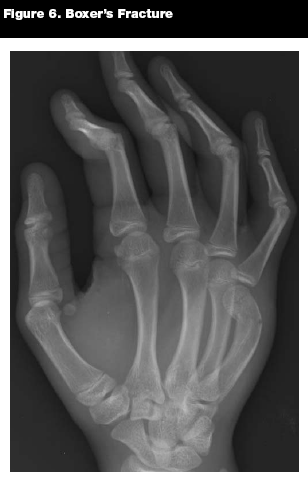

The boxer's fracture is a subset of metacarpal neck fractures that occurs in the fourth and/or fifth digits when a closed fist strikes an object. (See Figure 6.) This fracture is far more common in males. Approximately 25% of hand fractures in pediatric males are due to punching injuries, versus less than 2% in females.24

![]() |